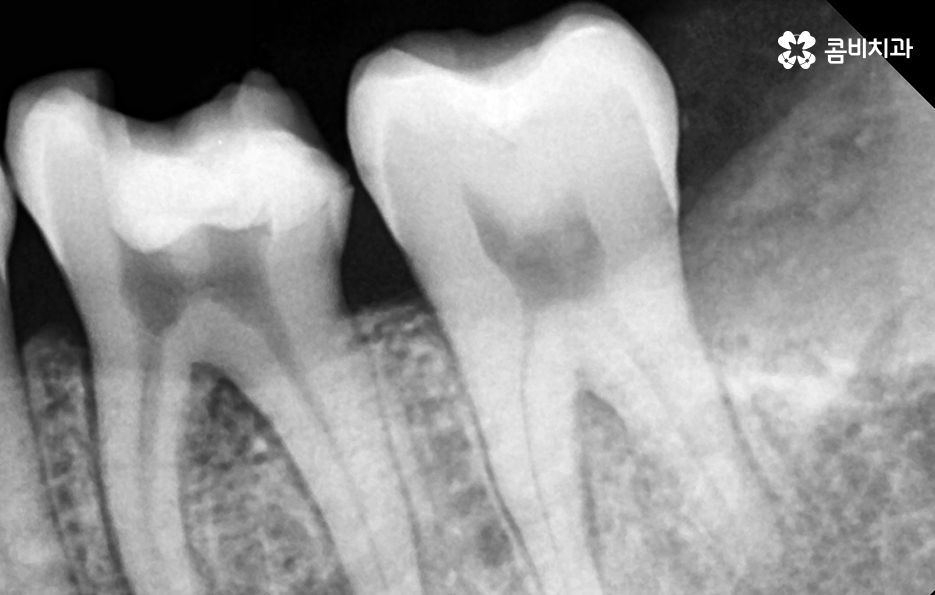

사랑니는 치아 중에서도 가장 마지막에 맹출이 되며 현대인들은 턱뼈가 좁아지는 추세이기 때문에 마지막에 자라는 사랑니는 위 케이스처럼 윗니의 경우 어금니의 높이 보다 다소 낮게 자라는 경우가 많고 아랫니의 경우 매복되어 있거나 누워서 자라는 사랑니의 형태로 자라는 경우가 많이 있는데요. 이러한 사랑니의 형태로 인해 어금니와 사랑니 사이에 이물질이 끼기 쉽고 칫솔질이 잘 닿지 않기 때문에 충치 뿐 아니라 잇몸 염증이 발생되는 경우가 많으며 사랑니 어금니 통증의 원인이 주변의 세균 증가로 인해 충치로 이가 썩은 경우부터 잇몸이 자주 붓고 염증이 심해지면서 통증을 느끼는 경우가 40,50대 이후에 흔하게 발생되는 사랑니와 인접한 어금니의 문제로 볼 수 있어요

일반적인 치아와 치아 사이는 이물질이 쉽게 침투하지 못하게 치아 사이의 공간이 많지 않고 치아 역시도 실링이 되어 있어서 미생물이 치아를 쉽게 뚫지 못하며 면역 물질로 인한 면역 작용도 있기 때문에 평소 칫솔질과 치실 사용, 주기적인 스케일링으로 어느정도 관리가 될 수 있는 것에 반하여 사랑니의 경우 어금니의 뿌리 부분에 가깝게 충치가 발생하기 쉽기 때문에 적절한 치료 시점을 놓치면 사랑니 어금니 통증이 두 치아 모두를 발치하게 되는 상황까지 발생될 수 있어요